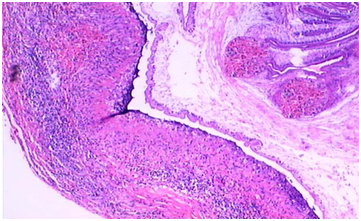

An excision biopsy of the swelling was done. On gross examination, the specimen showed a firm cyst surrounded by pale fibrous tissue. Cut section showed clear fluid filled cavity with a curved structure attached to the cyst wall. Microscopically, the cyst was surrounded by dense fibrous two layered wall showing lymphocytic infiltration. The tiny nodule contained within the cyst exhibited a coiled parasite within a connective tissue capsule (Figure 3). The diagnosis of subcutaneous cysticercosis was made.

Figure 3 Low power microscopy photograph showing a cross section of cysticerci entrapped in a fibrous capsule and surrounded by dense fibrous two layered wall showing lymphocytic infiltration and granulomatous reaction.